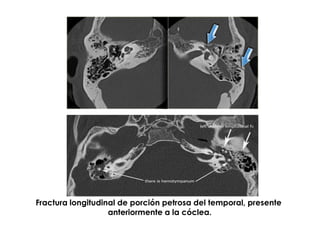

Fractura longitudinal de porción petrosa del temporal, presente

anteriormente a la cóclea.

Flecha amarilla, fractura longitudinal

de porción petrosa del temporal.